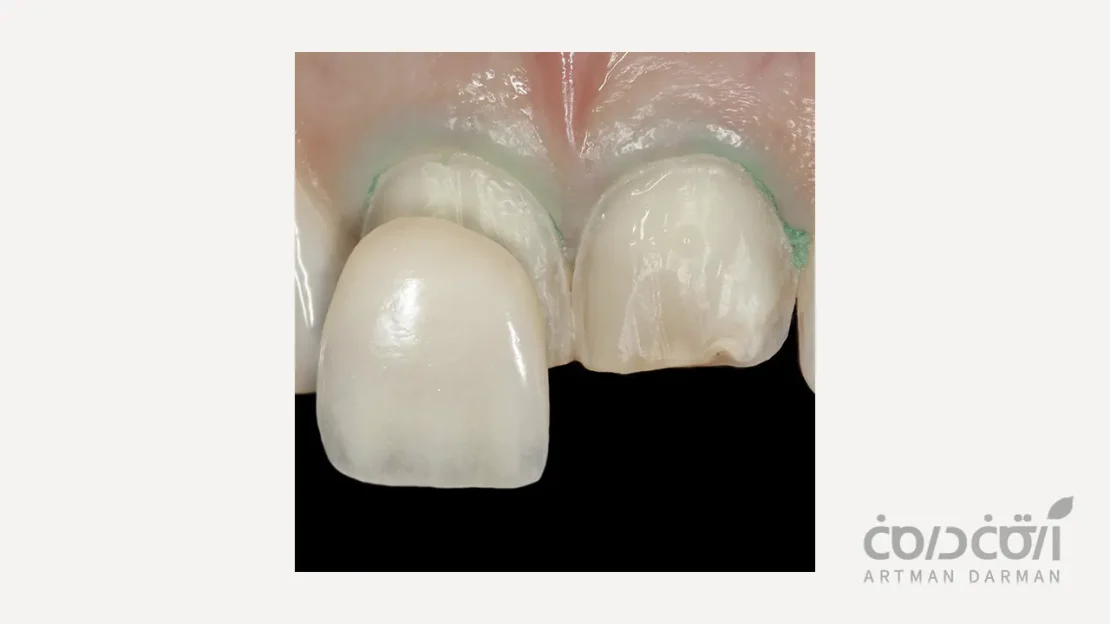

فرآیند تراش دندان برای لمینت، یک مرحله دقیق و کنترلشده است که با هدف حفظ حداکثری بافت سالم دندان انجام میشود. در نخستین گام، دندانپزشک پس از بررسی طرح لبخند و تعیین شکل نهایی لمینت، میزان تراش مورد نیاز را با دقت مشخص میکند. سپس با استفاده از ابزارهای ظریف، لایهای بسیار نازک از مینای سطح جلویی دندان تراشیده میشود تا فضای لازم برای قرارگیری لمینت ایجاد گردد. در این مرحله، ضخامت تراش معمولاً کمتر از یک میلیمتر است و تنها بخشهای ناهموار یا برجسته سطح دندان اصلاح میشوند. پس از اتمام تراش، سطح دندان پالیش و تمیز میشود تا برای قالبگیری دقیق و ساخت لمینت آماده گردد. این مراحل به گونهای طراحی شدهاند که زیبایی، استحکام و سلامت دندان تا حد ممکن حفظ شود.